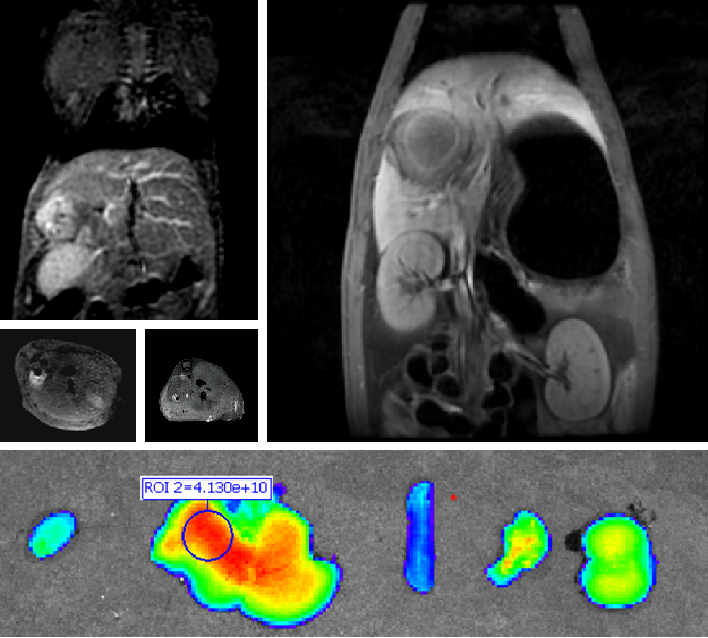

创新双模态造影剂(PL002)

太阳集团tcy8722自主研发的双模态造影剂PL002,已经获得美国FDA临床试验批件。PL002的研制首次提出通过整合磁共振技术,弥补现有荧光染料假阳性率高、透射深度有限等的短板,进而提升手术的精确性,降低手术过程中的风险,是全球首个获批临床试验的荧光/磁共振双模态造影剂。本项目预示着海南普利在造影剂领域的长期投入,并致力于开展独具特色的差异化国际化创新发展路径。